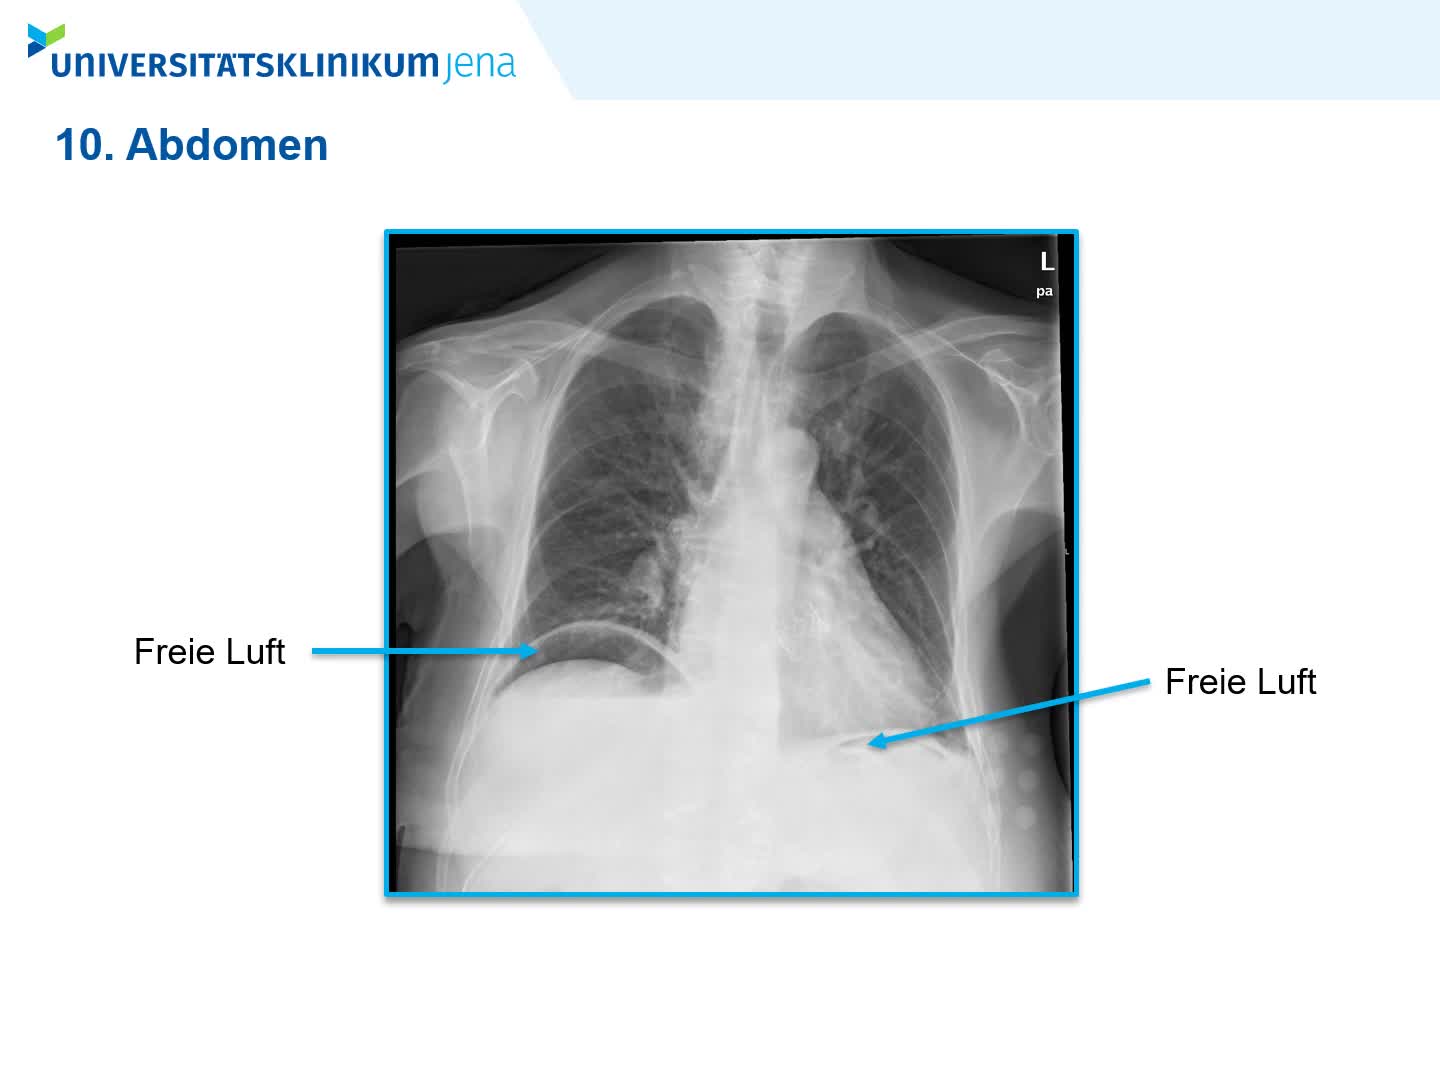

Carus Campus Rontgenbefundkurs Startet Am 22 6 Online Themen Rontgen Thorax Befundung Unterscheidung Von Erguss Infiltrat Stauung Pneumothorax Und Tumoren Unterschiede Im Stehen Und Liegend Thorax Rontgen Abdomen Kompakt Was Kann